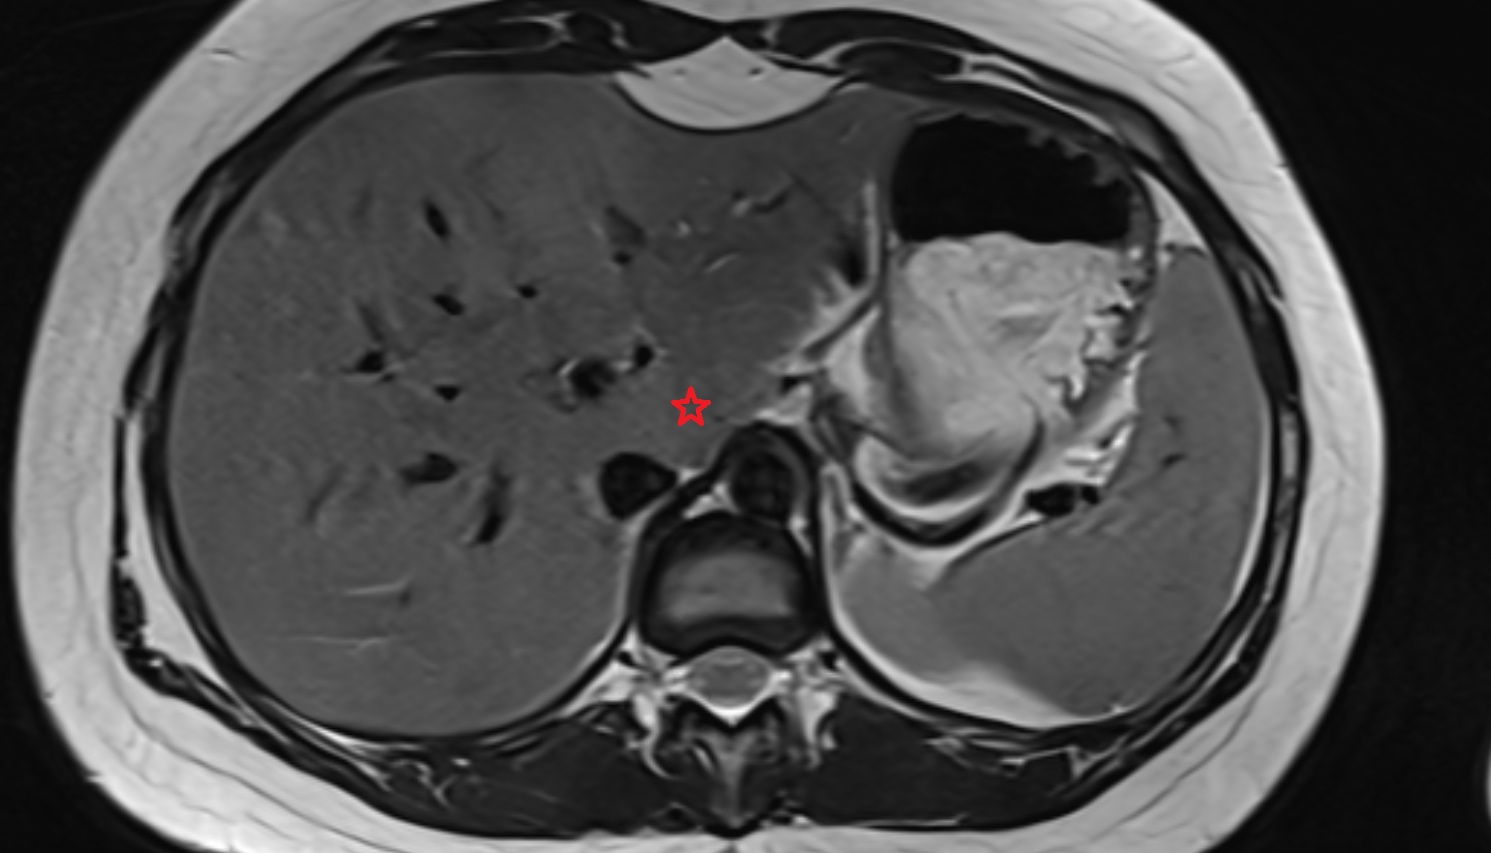

- Liver Segment I – Caudate lobe

- Liver Segment II – Left lateral superior segment

- Liver Segment III – Left lateral inferior segment

- Liver Segment IVa – Left medial superior segment

- Liver Segment IVb – Left medial inferior segment

- Liver Segment V – Right anteroinferior segment

- Liver Segment VI – Right posteroinferior segment

- Liver Segment VII – Right posterosuperior segment

- Liver Segment VIII – Right anterosuperior segment